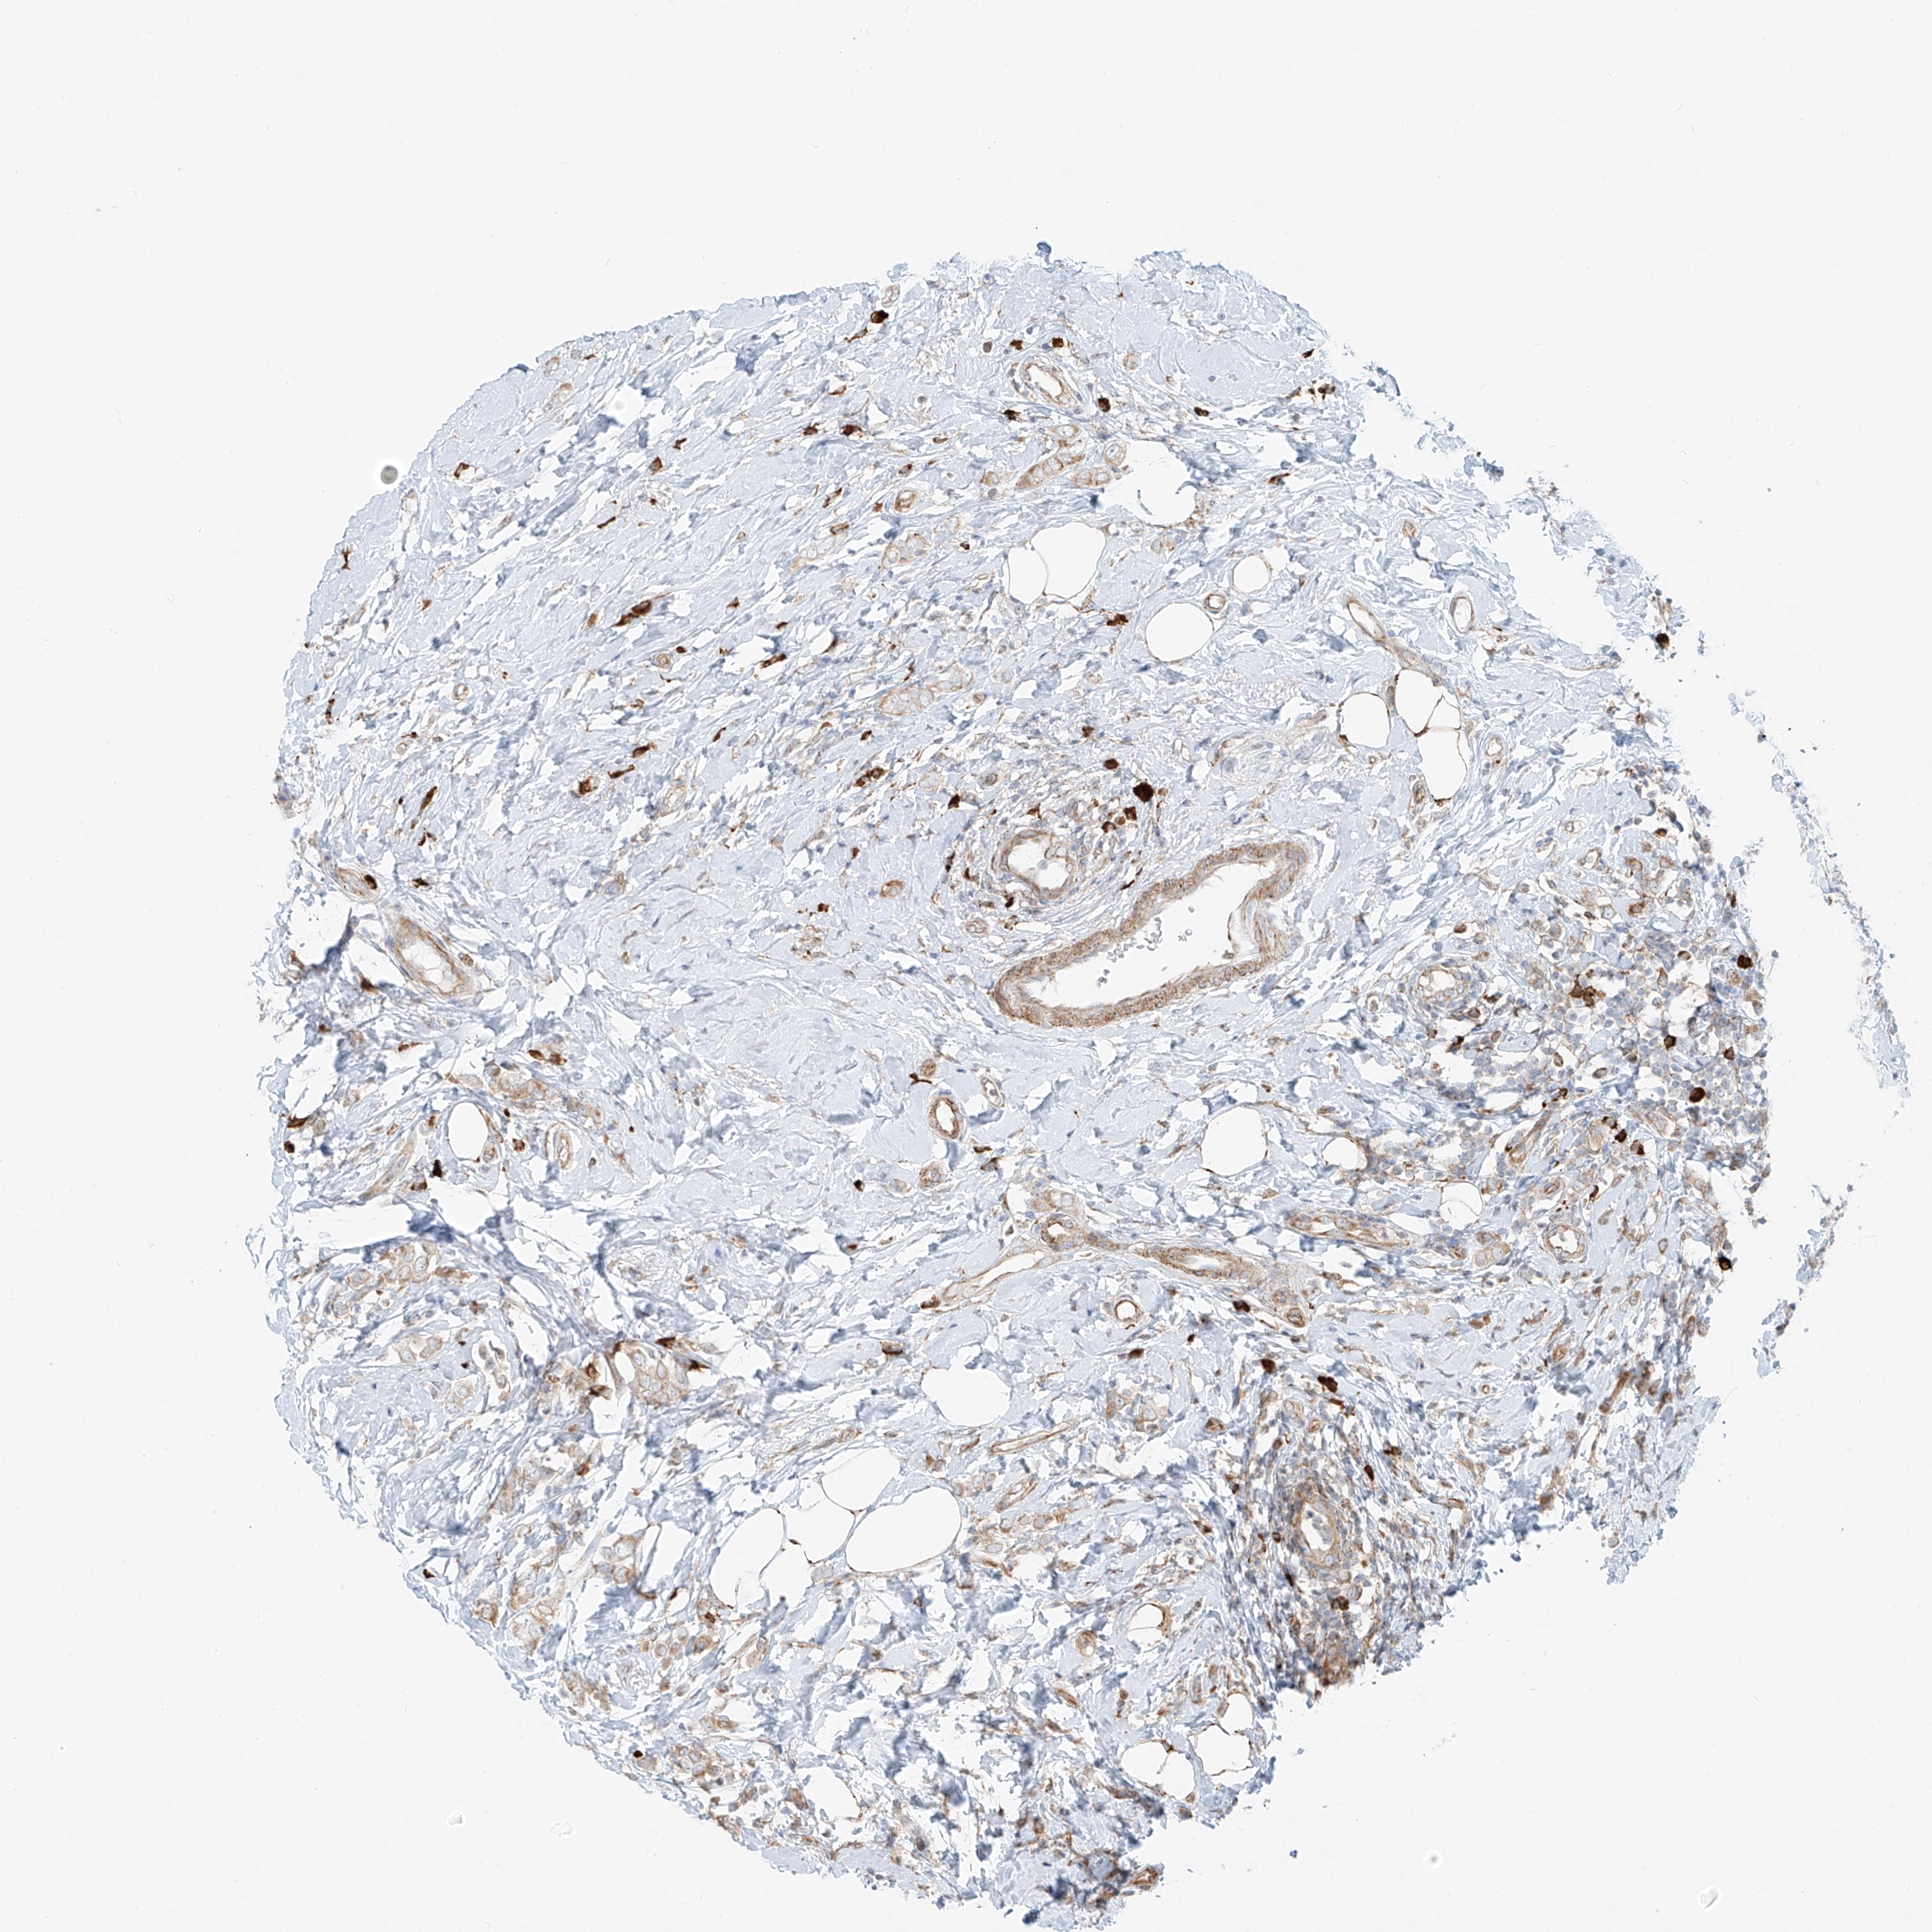

CANCER BREAST CANCER Show tissue menu

BRCA TCGA BRCA VALIDATION PROTEIN EXPRESSION